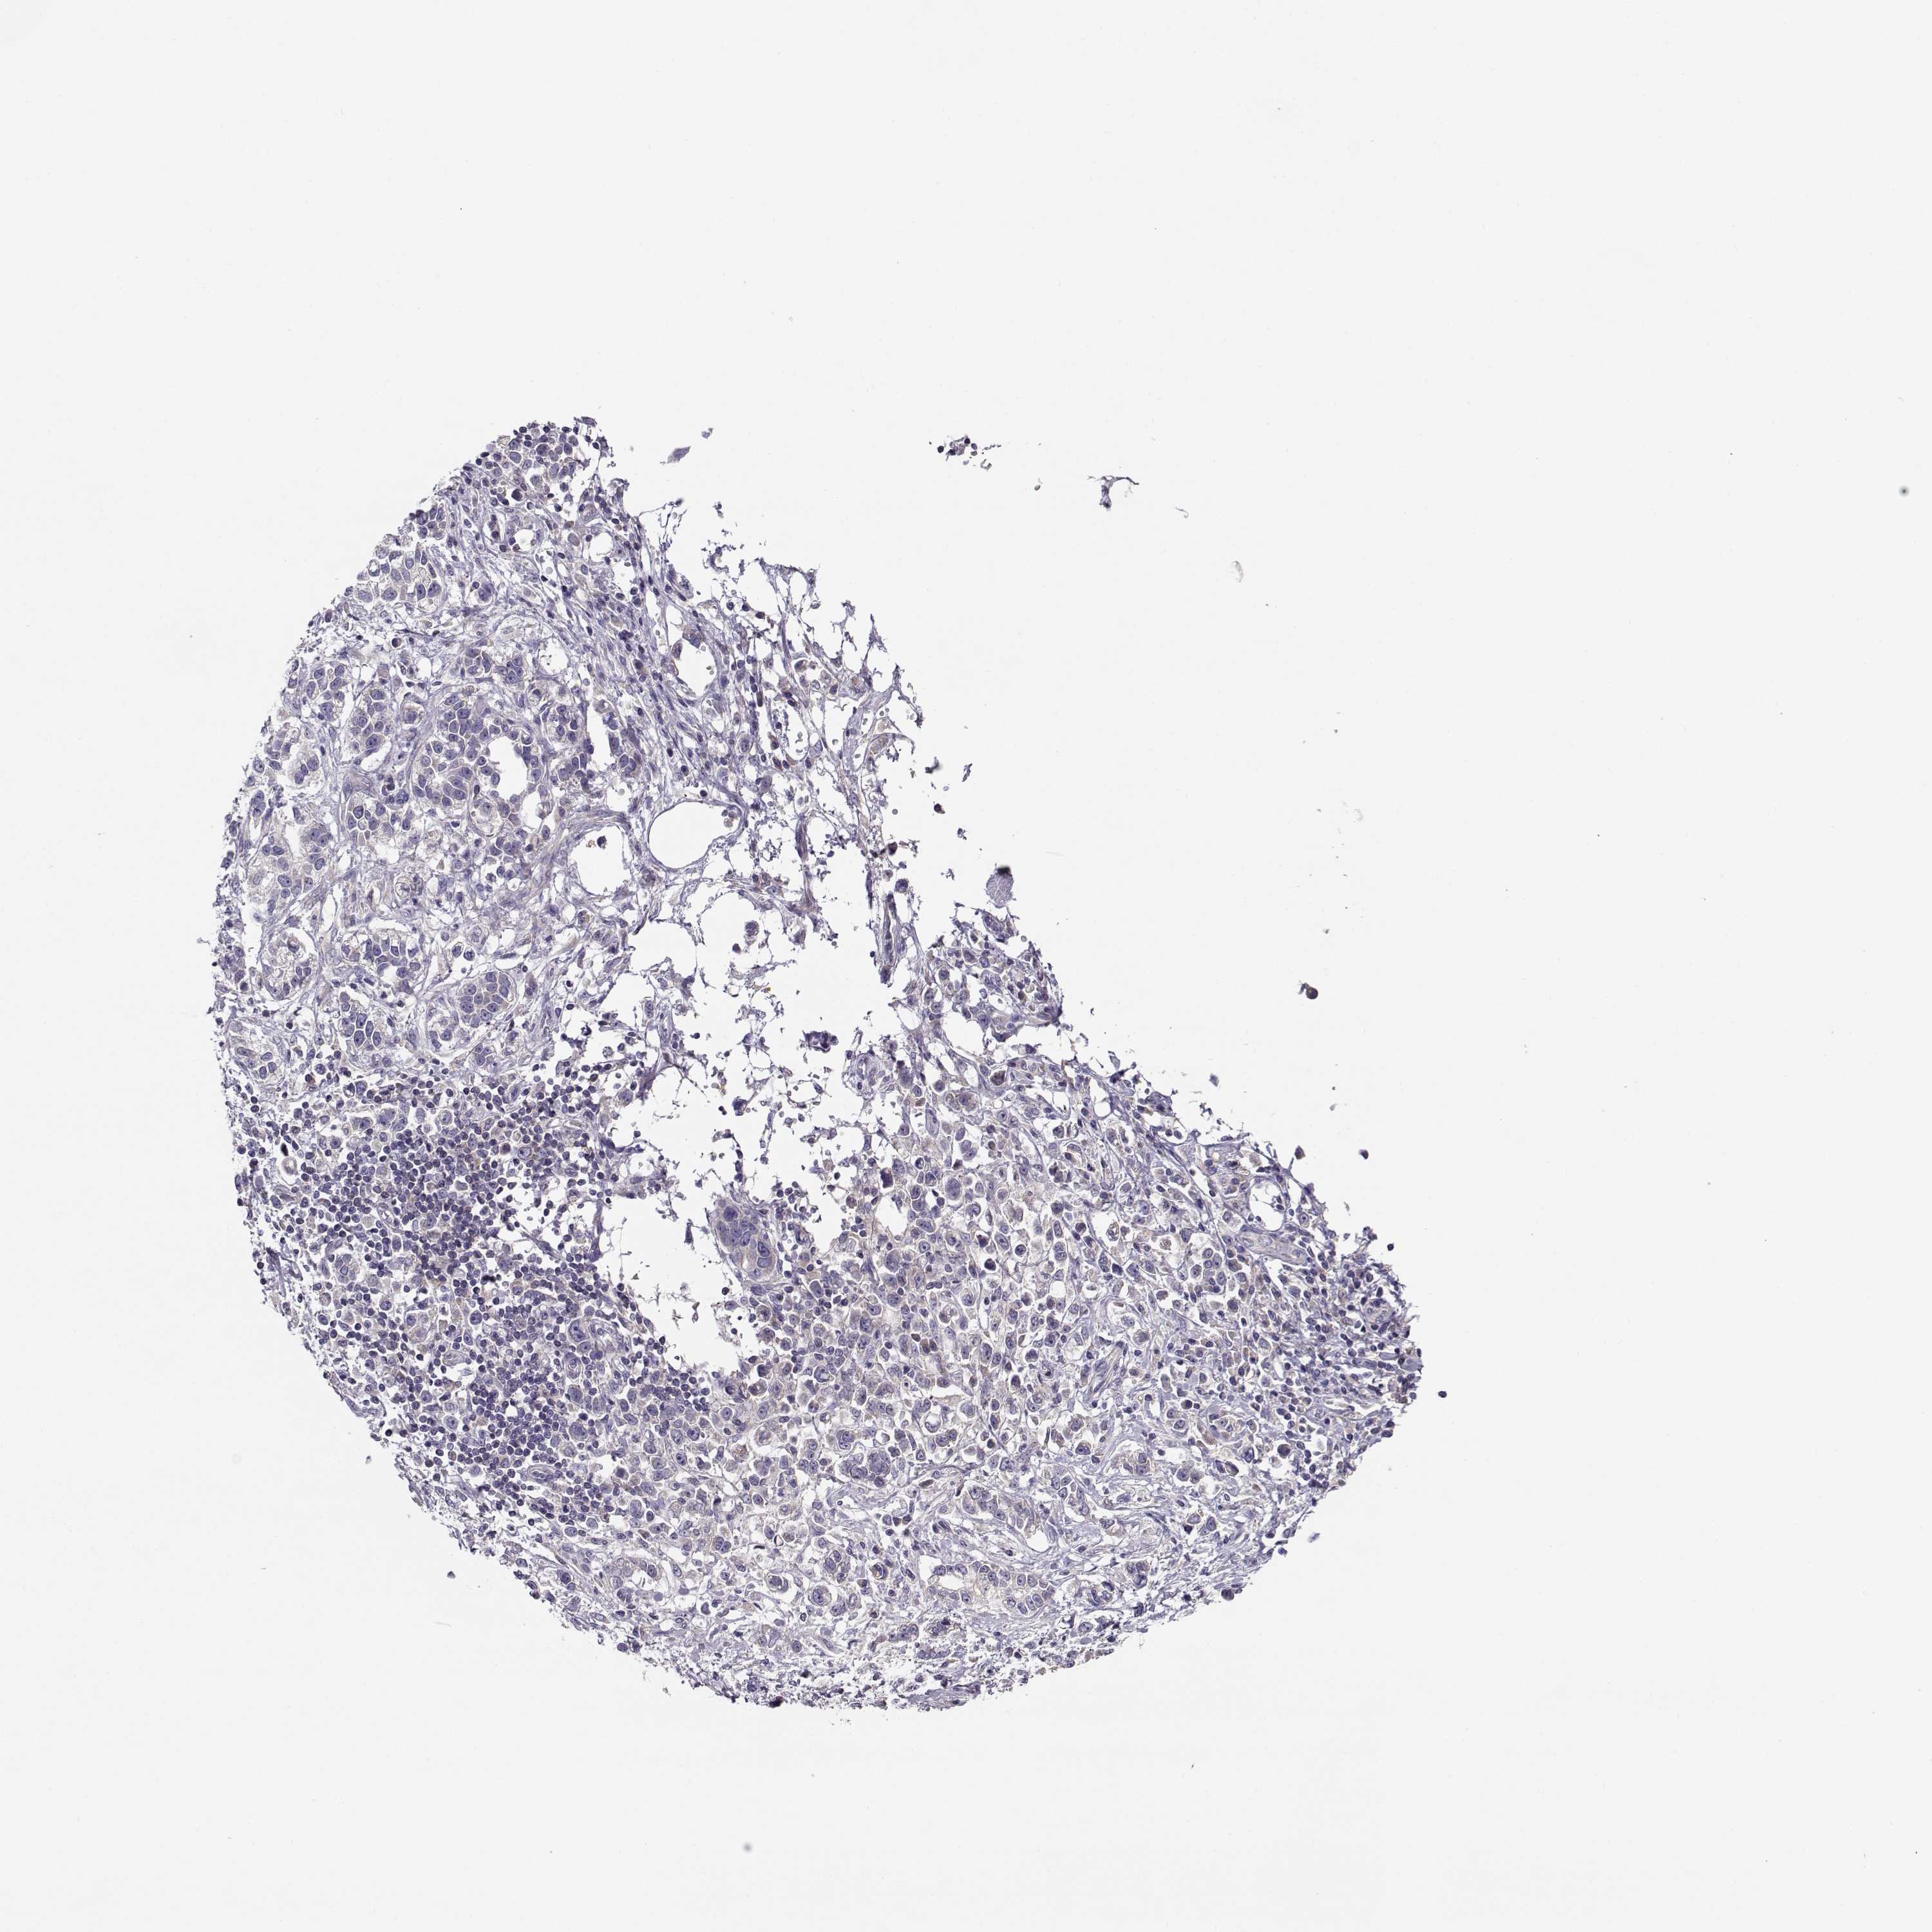

STOMACH CANCER - Protein expressioni

A mouse-over function shows sample information and annotation data. Click on an image to view it in a full screen mode. Samples can be filtered based on level of antibody staining by selecting one or several of the following categories: high, medium, low and not detected. The assay and annotation is described here.

Note that samples used for immunohistochemistry by the Human Protein Atlas do not correspond to samples in the TCGA dataset.

Antibody stainingi

Antibody staining in the annotated cell types in the current human tissue is reported as not detected, low, medium, or high, based on conventional immunohistochemistry profiling in selected tissues. This score is based on the combination of the staining intensity and fraction of stained cells.

Each image is clickable and will lead to virtual microscopy that enables deeper exploration of all samples and also displays staining intensity scores, fraction scores and subcellular localization as well as patient and tissue information for each sample.

Antibody HPA073303

Staining

High

Medium

Low

Not detected

Intensity

Strong

Moderate

Weak

Negative

Quantity

>75%

75%-25%

<25%

None

Location

Nuclear

Cytoplasmic/membranous

Cytoplasmic/membranous,nuclear

Adenocarcinoma, NOS